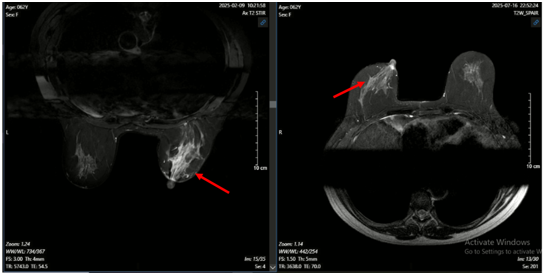

MRI động học tuyến vú: Hiện không thấy tổn thương ngấm thuốc vú phải – đáp ứng hoàn toàn sau điều trị. Hiện không thấy tổn thương nghi ngờ ác tính trên phim cộng hưởng từ tuyến vú trái (BIRADS 1). Hạch nách phải (không thay đổi so với phim cũ).

Hình 5. Hình ảnh MRI u vú trước (bên trái) và sau điều trị (bên phải): Khối ngấm thuốc ¼ dưới ngoài vú phải trên phim MRI trước điều trị hiện không thấy trên phim MRI sau điều trị.